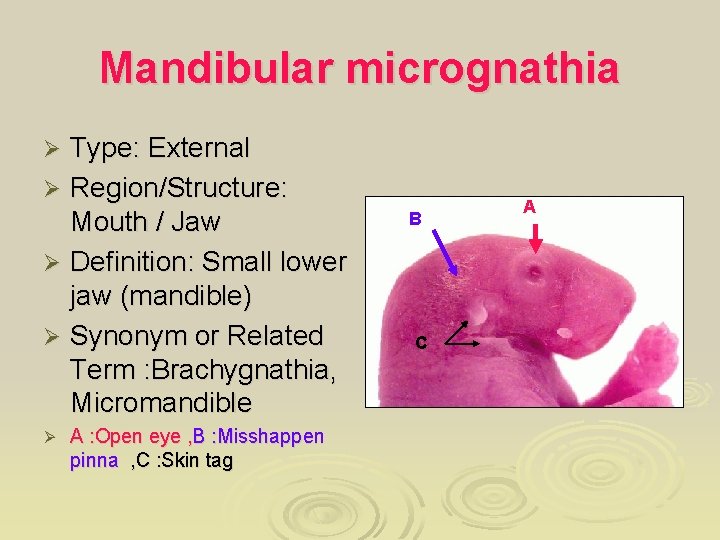

Mandibular micrognathia Type: External Ø Region/Structure: Mouth / Jaw Ø Definition: Small lower jaw (mandible) Ø Synonym or Related Term : Brachygnathia, Micromandible Ø Ø A : Open eye , B : Misshappen pinna , C : Skin tag B C A